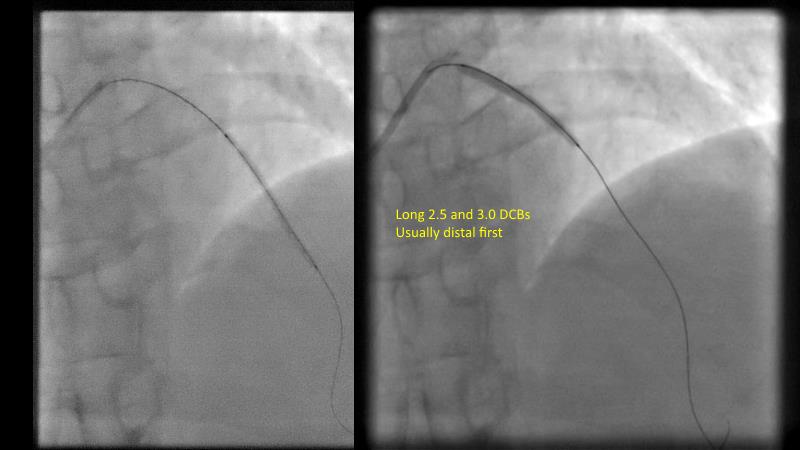

DES and DCB, can these two technologies be complementary for the treatment of the same patient? What are the advantages and how to proceed? You will know everything by watching this presentation based on concrete cases.